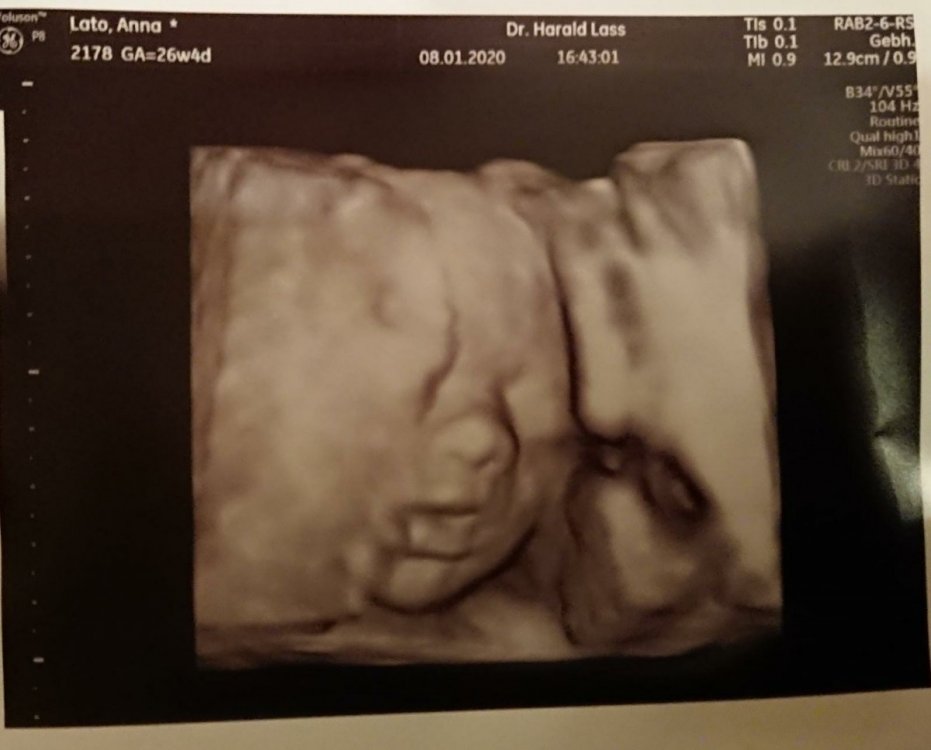

2. Juz wszystko w porzadku 🙂 widze wszystkie posty i moge sie zalogowac. Jestem wlasnie po wizycie. Wszystko jest w porzadku. Mala wazy 1005g 🙂 Szyjka dluga na 4,4cm i zamknieta. Wody plodowe, przeplywy bardzo dobre. Jutro ide na glukoze, na nastepna wizyte (30.1) mam przyjsc z zastrzykiem immunoglobulina Rh. No i szczepienie przeciw krztuscowi chce jeszcze zalatwic pod koniec stycznia. W przyszlym tygodniu mam termin w szpitalu z polozna. Black Panther, u mnie po operacji tarczycy troche trwalo, zeby ustawic prawidlowo dawke. Raz bylo za malo, raz za duzo. Ale po jednej tabletce to raczej nie jest mozliwe. Magdaa, gratuluje coreczki kolezanke, chociaz porod faktycznie ciezki... Mama88, oj nie zawsze mam sily, a czasem plecy daja mi mocno popalic, ale nie zastanawiam sie specjalnie tylko jakos sie zwlekam 😉